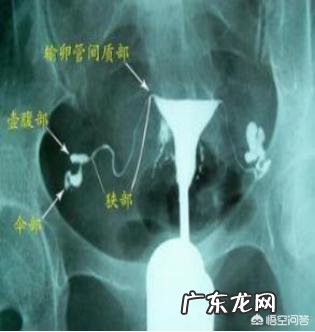

2.“银汉迢迢忍顾鹊桥路?”第二名输卵管 。

输卵管对精子和卵子来讲是自然妊娠的“鹊桥之路” 。它是“金风”、“玉露”相逢之地,是生命诞生和生长发育最初阶段的温床,在这里要完成受精卵结合并发育成分裂球的蜕变,要度过宝贵的72小时后成长为早期囊胚而进入营养更加肥沃的宫腔 。在对不孕症因素的分析后发现约25%的不孕症与输卵管阻塞和粘连有关 。而导致输卵管病变的因素包括感染(主要为沙眼衣原体感染,结核感染)、输卵管积水、子宫内膜异位症、盆腔手术史和罕见的子宫肌瘤 。因此在平素的生活中女性要注意温柔以待这座“桥”,注意卫生,避免或减少不必要的流产,爱护及保护好输卵管这块生命圣地 。